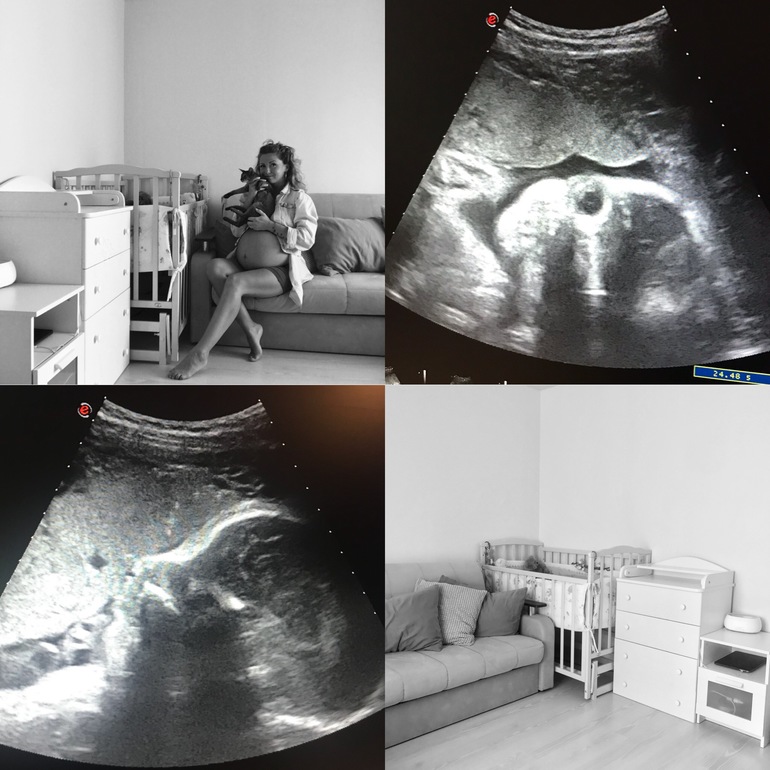

Так что 10 сентября, в этот понедельник, я тихонько беру свои пакеты и отправляюсь в роддом.

Ходить очень тяжело. Коленки ноют, спина отваливается, одышка и прочие прелести последних месяцев беременности.

Изжога так и не прошла. Все пророчат кудрявую волосатую Дочь -посмотрим. С сыном даже и не знала что такое кислота в желудке и ее подъем без опускания обратно.

Сон нарушен, хотя нет.. нарушен так, что стал графиком ( 2 подъема). Первый подъем в 1-2 ночи, а второй 4-5 утра. После последнего я могу и не заснуть. Днем вырубает после 12, но увы, а вот пролежав до часу могу и уснуть. Вообще страшно конечно смотреть на вечного двигателя, который стал тюленем. Но это ж временно 😝

Оттечность то немного спадает, то вновь проявляется по полной программе. Ноги и руки от этого конечно же страдают. Большей частью руки. Бывает проснусь ночью от жуткого немения рук ( от плеча до кистей). Сажусь и начинаю растирать ( насколько это вообще возможно). Пальцы рук, особенно на правой стороне ( там у меня мигрень проявляется) вообще не согнуть, только через боль и хруст. Читала в инете, что это какой-то синдром и все из-за оттечности.

Наверное всех к этому сроку посещает состояние страха, нервозности, паники. Вот и я пришла. Меня колбасит по полной, но я держусь. С сыном отмечаем последнии дни вдвоём, так как после это в любом случае будет уже втроём ( даже если папа будет на работе). Так что сидя печем блины 🥞, да шоколадные печенья. Он даже не пошёл гулять ( что очень не похоже на него).

Печальный пост выходит 🤔 Выдыхаю. Скоро станет все ясно, понятно. Скоро здоровенькая дочь будет на руках.

Общая прибака 12 кг ( но сейчас пошел обратный процесс скидывания кг)

Обхват живота целый метр.